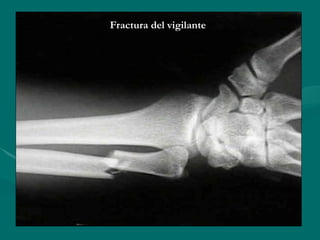

Fractura del vigilante

( Nightstick )

• Fractura aislada de la diafisis de la

Fractura aislada de la diafisis de la

ulna

• Como resultado de un golpe directo

Como resultado de un golpe directo

sobre el antebrazo

• Ocurre cuando se trata de proteger

Ocurre cuando se trata de proteger

la cabeza del golpe por un objeto

contundente

Características Radiográficas

Características Radiográficas:

Comúnmente en tercio distal

• Usualmente transverso, puede tener

Usualmente transverso, puede tener

tercer fragmento en ala de mariposa

• Es común la luxación lateral segmento

Es común la luxación lateral segmento

proximal de radio

Fractura del vigilante Fracturadel vigilante ( Nightstick ) ( Nightstick ) • Fractura aislada de la diafisis de la Fractura aislada de la diafisis de la ulna ulna • Como resultado de un golpe directo Como resultado de un golpe directo sobre el antebrazo sobre el antebrazo • Ocurre cuando se trata de proteger Ocurre cuando se trata de proteger la cabeza del golpe por un objeto la cabeza del golpe por un objeto contundente contundente

Fractura del vigilante Fracturadel vigilante ( Nightstick ) ( Nightstick ) Características Radiográficas Características Radiográficas: : • C Comúnmente en tercio distal omúnmente en tercio distal • Usualmente transverso, puede tener Usualmente transverso, puede tener tercer fragmento en ala de mariposa tercer fragmento en ala de mariposa • Es común la luxación lateral segmento Es común la luxación lateral segmento proximal de radio proximal de radio